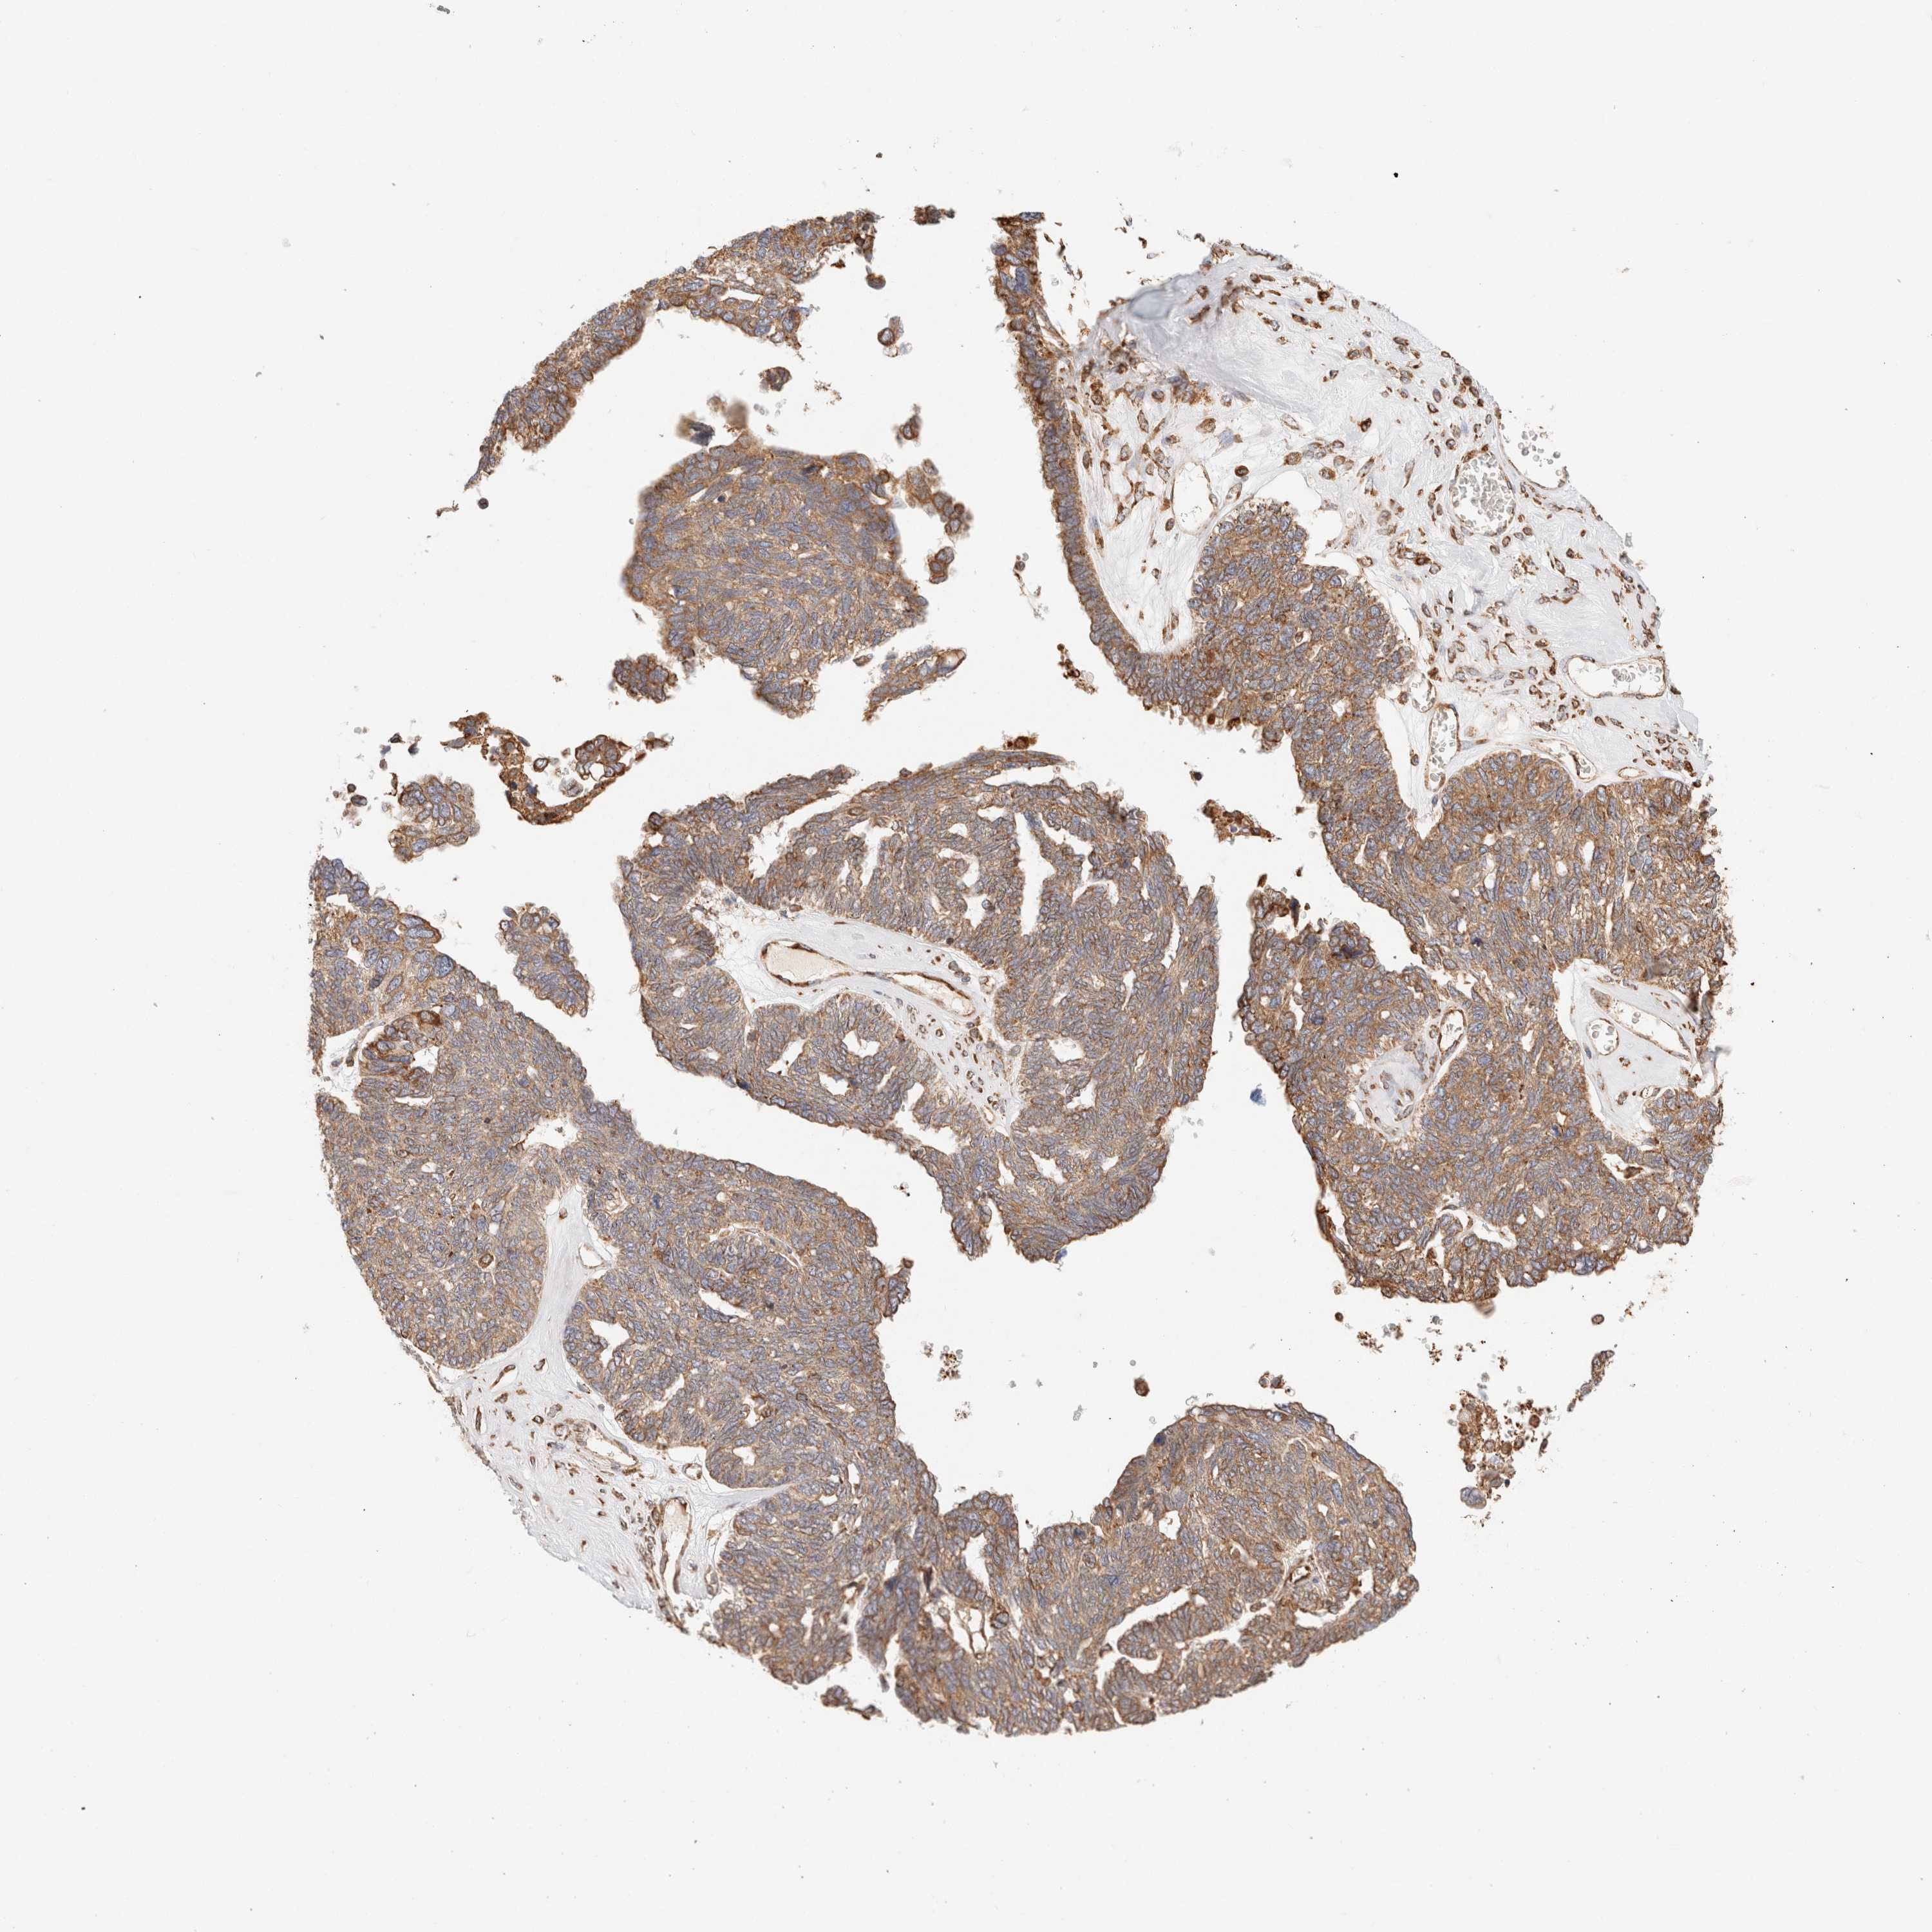

OVARIAN CANCER - Protein expressioni

A mouse-over function shows sample information and annotation data. Click on an image to view it in a full screen mode. Samples can be filtered based on level of antibody staining by selecting one or several of the following categories: high, medium, low and not detected. The assay and annotation is described here.

Note that samples used for immunohistochemistry by the Human Protein Atlas do not correspond to samples in the TCGA dataset.

Antibody stainingi

Antibody staining in the annotated cell types in the current human tissue is reported as not detected, low, medium, or high, based on conventional immunohistochemistry profiling in selected tissues. This score is based on the combination of the staining intensity and fraction of stained cells.

Each image is clickable and will lead to virtual microscopy that enables deeper exploration of all samples and also displays staining intensity scores, fraction scores and subcellular localization as well as patient and tissue information for each sample.

Antibody HPA007641

Antibody CAB022464

Cystadenocarcinoma, serous, NOS

Carcinoma, endometroid

Cystadenocarcinoma, mucinous, NOS

Carcinoma, NOS